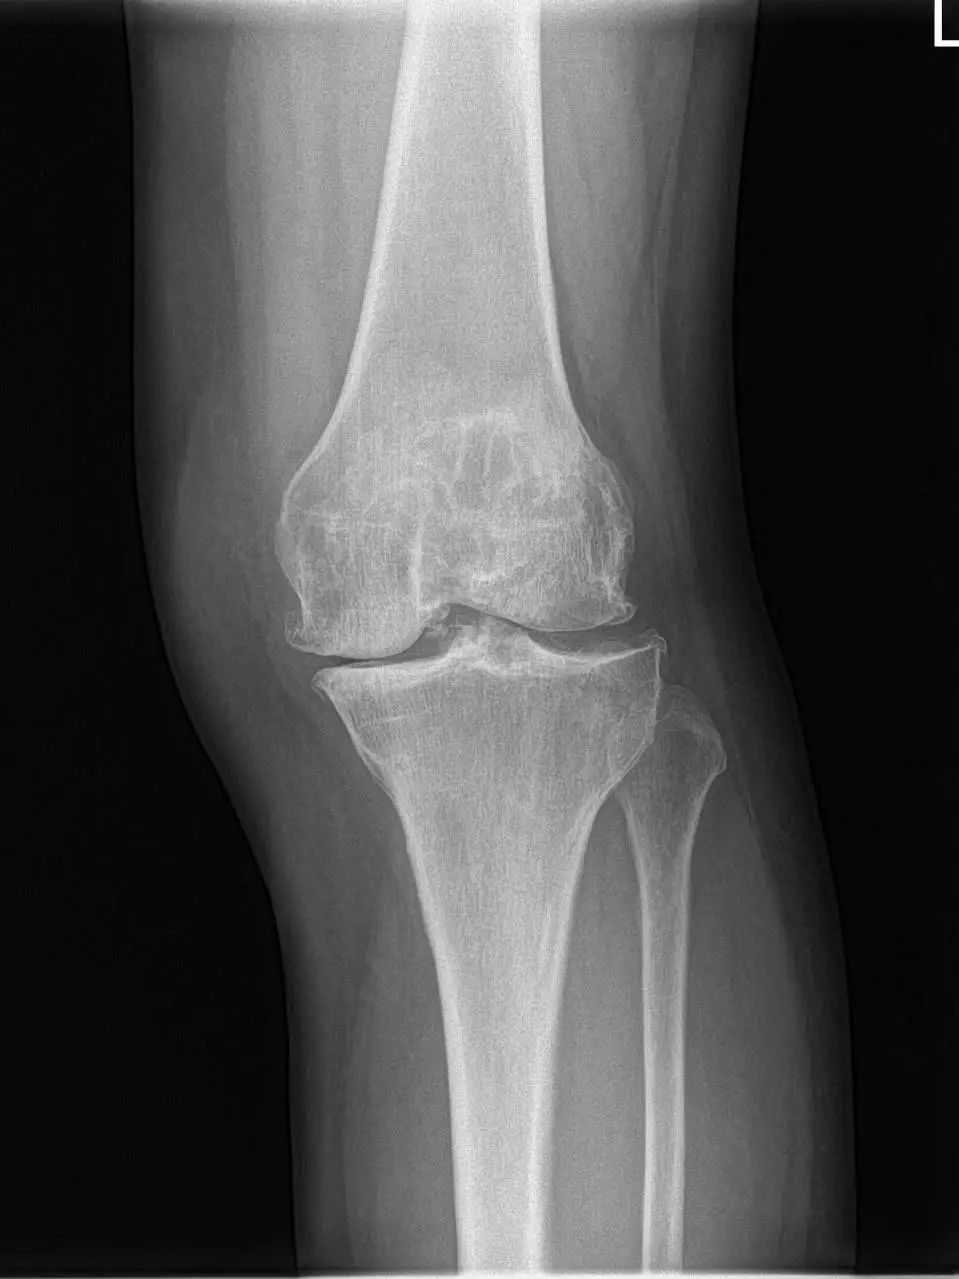

74岁的吕阿姨膝关节疼痛10余年,屈伸活动受限,外院就诊止痛药等保守治疗效果欠佳,拍片提示膝退行性骨关节炎。近日,她慕名来到上海市同济医院骨关节外科中心程飚主任门诊,程飚主任结合患者症状,影像学结果,体格检查,发现吕阿姨主要问题集中在膝关节内侧及髌股关节,膝关节外侧尚可。

67岁的邵阿姨,双膝关节疼痛10余年,疼痛主要集中在屈伸膝关节时髌骨下。长期口服及外用药物治疗效果欠佳,反复加重,双膝的x线检查提示主要为髌股关节的退行性骨关节炎。程飚主任结合患者症状,影像学结果,体格检查,发现邵阿姨主要问题集中在髌股关节,膝关节间隙,内外侧髁,胫骨平台均可,为解决邵阿姨痛苦,尽可能保留关节,程飚主任决定对邵阿姨进行双侧膝关节的髌股关节表面置换,截骨量较少,邵阿姨第二天就能下地活动了,屈伸关节也不痛了,对手术疗效表示非常的满意。

部分膝关节置换手术目前已是非常成熟的治疗方法,亦属于保膝治疗的一种。主要包括单髁置换,髌股关节置换。单髁置换主要把膝关节内侧髁或者外侧髁表面已经磨损的部分替换成金属的假体和高分子聚乙烯耐磨垫片。髌股关节置换主要把髌股关节表面已经磨损的部分替换成金属的假体。

主要为退行性骨关节炎的患者,病变局限于内侧或者外侧胫股关节,可行单髁置换;

病变局限于髌股关节的患者,可行髌股关节表面置换;

同时有髌股关节及单侧髁的病变,可行单髁+髌股关节表面置换。